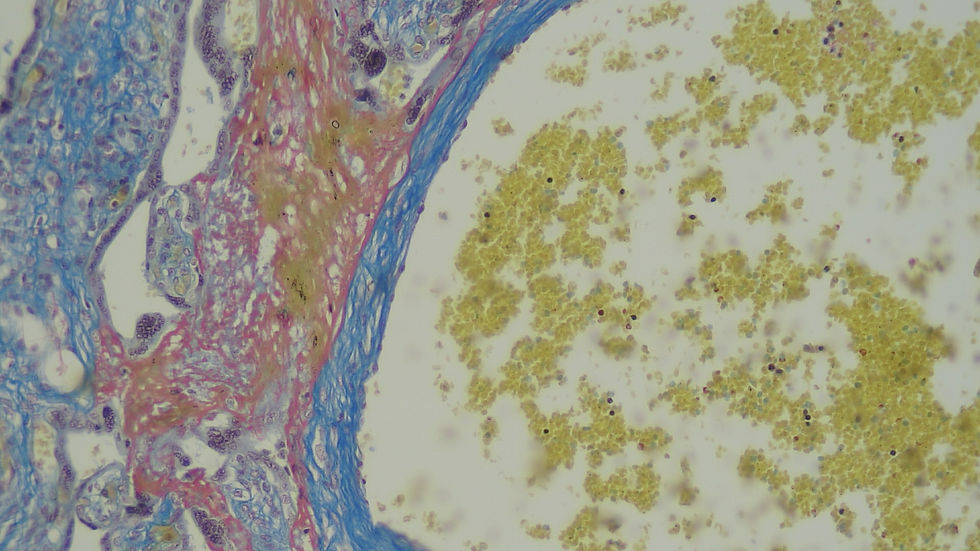

-Masson Trichrome